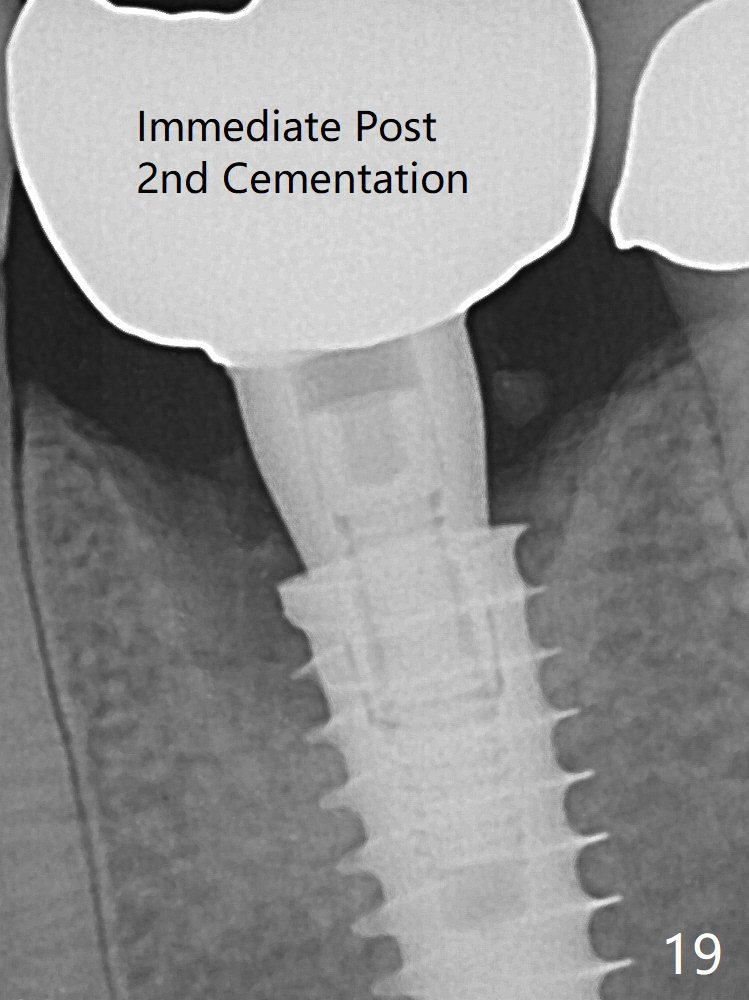

The gingiva looks healthy 8 months postop (3 months post cementation (after abutment screw retightening and addition of porcelain to proximal surfaces, Fig.12).  New bone has apparently covered the implant plateau (Fig.13 arrows). Bone density between threads increases 9 months post cementation (Fig.14).  There is 2 mm bone superior to the implant plateau mesial and distal 1 year 9 months post cementation (Fig.15,16).  The crown/abutment is loose 3 times (3 months (Fig.14), 11 months (between Fig.14 and 15) and 2 years 3 months post cementation).  In spite of being stable 3 years 10 months post cementation, a smaller abutment is placed (Fig.17 (PA), 18 (BW)) with impression for a new crown.  After intraoral cementation, the new crown/abutment is removed for residual cement removal.  When the complex is reseated, it is not smooth, probably due to proximal undercut.  Fortunately the abutment appears to be completely seated, followed by 20 Ncm torque (Fig.19).